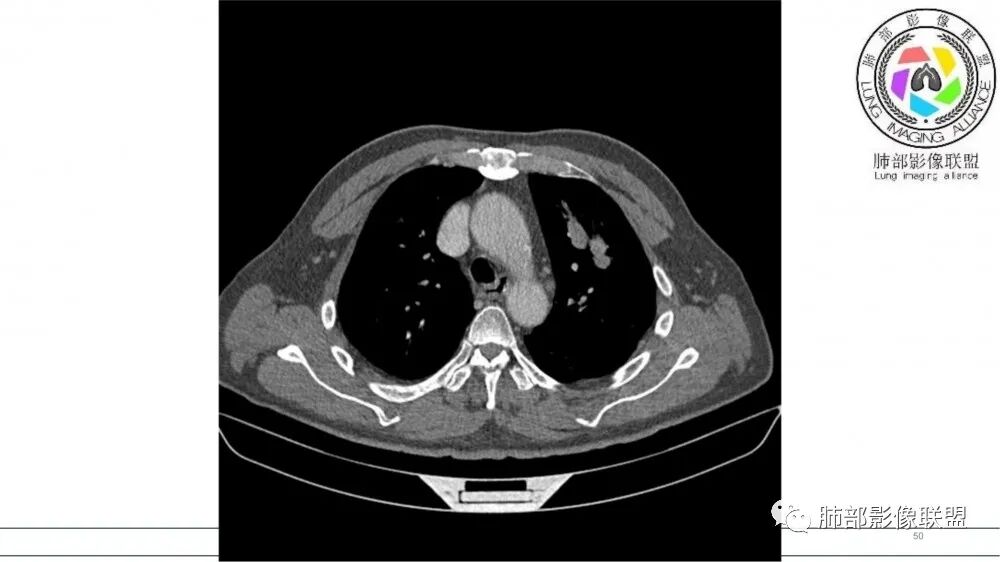

左肺上叶前段支气管内铸形生长软组织影,增强后均匀强化,远侧见斑片状磨玻璃影。考虑恶性病变,粘表?粘液腺?

老年男性,左肺上叶前段支气管内铸形阴影,增强后病灶不均匀强化,内部有坏死?远端可见斑片状阴影(阻塞性肺炎)。考虑恶性病变,老年人,鳞?类癌?粘表不能排除。

左肺上叶前段支气管杵状指样扩张,内见实性组织阻塞性,并强化明显,边缘饱满,周边多发小斑点影,小花小草征,老年男性,长期吸烟史,方向恶性,首选支气管内浸润鳞Ca可能性大。

老年男性,肺气肿,吸烟史,左肺上支气管腔内铸型高密度影,呈指套状,远端多发树芽,增强不均匀强化,考虑鳞癌,鉴别小细胞癌

B3指套征,常规不是鳞癌就是ABPA,有强化丶血管造影征,倾向于鳞癌

病灶沿支气管生长,强化不均匀,坏死不明显,血管自然进入,支持恶性,小在先,鉴别淋巴瘤

老年男性,吸烟史,左肺上叶支气管塑形生长肿块,整体边缘较圆钝,不均匀强化,血管走形,形态较纤细,病灶远端可见花草样改变,恶性,先考虑小细胞癌鉴别鳞癌

老年男性,影像支气管铸型,血管造影,考虑恶性,鳞癌,小细胞。

老年男性,长期吸烟史。左上肺前段沿支气管走形的指套样病变,增强可见病灶强化(排除结核、ABPA(也无气喘症状)),远端多发点状高密度影。考虑恶性肿瘤,鳞癌可能性大。

指套征,扩张支气管内软组织强化,远侧肺野阻塞性炎,纵隔、左肺门肿大淋巴结;老年男性,吸烟,考虑鳞癌,鉴别小

老年男性,术前检查肺气肿背景,左肺上叶结节,沿支气管蠕虫样生长,左肺门及纵隔淋巴结肿大,增强扫描不均匀强化,血管包绕,结合吸烟史,考虑小细胞肺癌。

指套征:是影像征象,胸部平片表现为手指状密度增高影,以肺门为中心呈放射状分布,CT显示扩张支气管内低密度黏液栓形成或实性病变,呈管状、树枝状或卵圆形密度增高影;支气管扩张伴近端梗阻时,扩张支气管内部黏液分泌物不能排出而形成。可以伴随远端空气潴留征、阻塞性炎症。

研究报道,中心型 SCLC 经 CT 扫描后通常支气管表现为鼠尾样狭窄,肺门或纵隔肿块明显,由于肿块沿管壁生长表现为顺延支气管形态的不规则形状。病灶相对特征性影像学表现比如鸭蹼状、腊肠状、葫芦状及葡萄状改变,可以出现血管包埋,很少有空洞、空泡,较少引发肺不张,阻塞性炎症成都较轻。与一般肺癌比较,恶性程度高,侵袭力强、病灶很小就容易远处转移!Herzberg 等[19]研究指出,20%以上 SCLC 倍增时间短,预后不良。